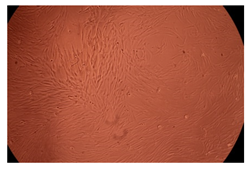

The results of the cytotoxicity assay, given in Figure 5, indicate that the tested PMs at all three established concentrations (10, 50, and 100 µg/mL) did not show cytotoxic effects on fibroblast cells at either 24 or 48 h after incubation. The percentages of cell viability were high, over 90%, in cells that were exposed to a concentration of 10 µg/mL for 24 h for all tested materials. Even at 48 h after incubation, the percentage of cell viability was as high as 90.4% in cells exposed to a concentration of 10 µg/mL for the Cop B sample. For both drug-loaded PMs, the cell viability decreased slightly at all tested concentrations. It also appears that the Dorzolamide-loaded PMs have slightly lower cell viability as compared to IMC-loaded PMs. Micrographs of the fibroblast cells after incubation times of 24 and 48 h are provided in Table 2.

Table 2.

Micrographs of fibroblast cells after 24 and 48 h incubation times, respectively.

As the cell viability values are all over 80%, the results indicate that the PMs, at the established concentrations, can be used successfully for in vivo biomedical applications.